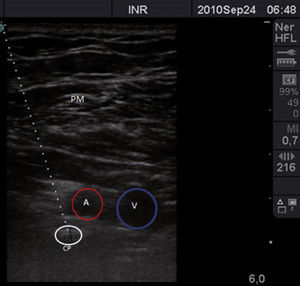

Inicialmente, los pacientes se dividieron en 2 grupos, elegidos de forma consecutiva: grupo con brazo en abducción y grupo con brazo en aducción. Se utilizó un ultrasonido con transductor lineal de alta frecuencia (13-15MHz). Los pacientes se colocaron en posición supina, monitorizados de manera no invasiva, y se mantuvieron bajo sedación consciente. De forma consecutiva, se colocó el brazo en aducción (fig. 1) o en abducción (brazo flexionado a 90°) (fig. 2). El eje largo del transductor se colocó en el vértice de la fosa deltopectoral, perpendicular a esta región y por debajo de la coracoides en el plano parasagital. Las estructuras neurovasculares se identificaron en el eje transversal. Se visualizó la arteria axilar como referencia para determinar los cordones del plexo braquial, en un plano superior se identificaron el músculo pectoral mayor y el músculo pectoral menor. La sonoanatomía encontró la vena axilar medial y caudal a la arteria axilar (fig. 3).